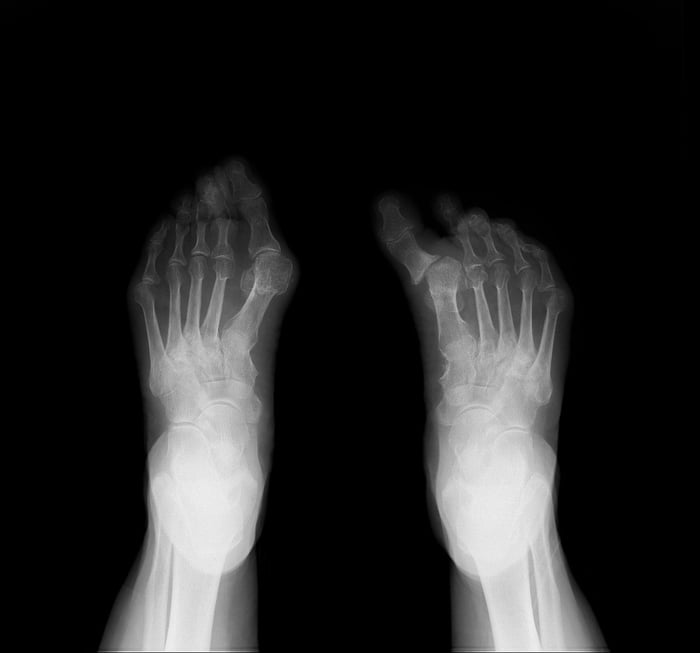

Alluce varo e valgo

L'alluce è sicuramente fra i casi più frequenti e più conosciuti di valgismo, ma esiste anche la condizione opposta. Riassumendo:

- Alluce valgo: deviazione laterale dell’alluce verso le altre dita, spesso associata a prominenza mediale della testa del primo metatarso. È la deformità del primo raggio più frequente, soprattutto nella popolazione femminile.

- Alluce varo: deviazione mediale dell’alluce, più rara, talvolta post-chirurgica o congenita. Quando è congenito è considerato un residuo ancestrale della nostra evoluzione. Infatti, il varismo dell’alluce accentua le capacità prensili rendendo il piede più simile ad una mano, ma meno adatto alla stazione eretta. Talvolta può essere associato a un piede cavo o ad alcune patologie neuromuscolari.